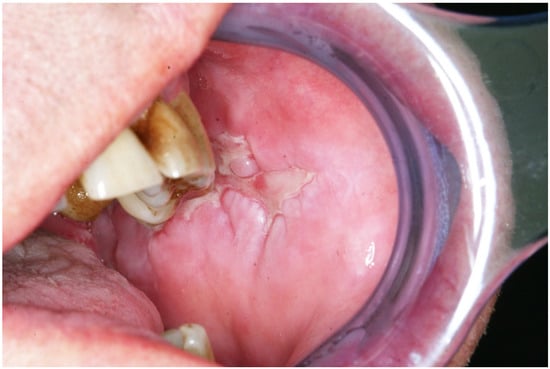

2.4. Paraneoplastic Pemphigus (PNP)

| Clinical features | Painful mucosal erosions with or without a multiform skin eruption characterized by blisters and erosions, occurring in association with an occult or evident neoplasm |